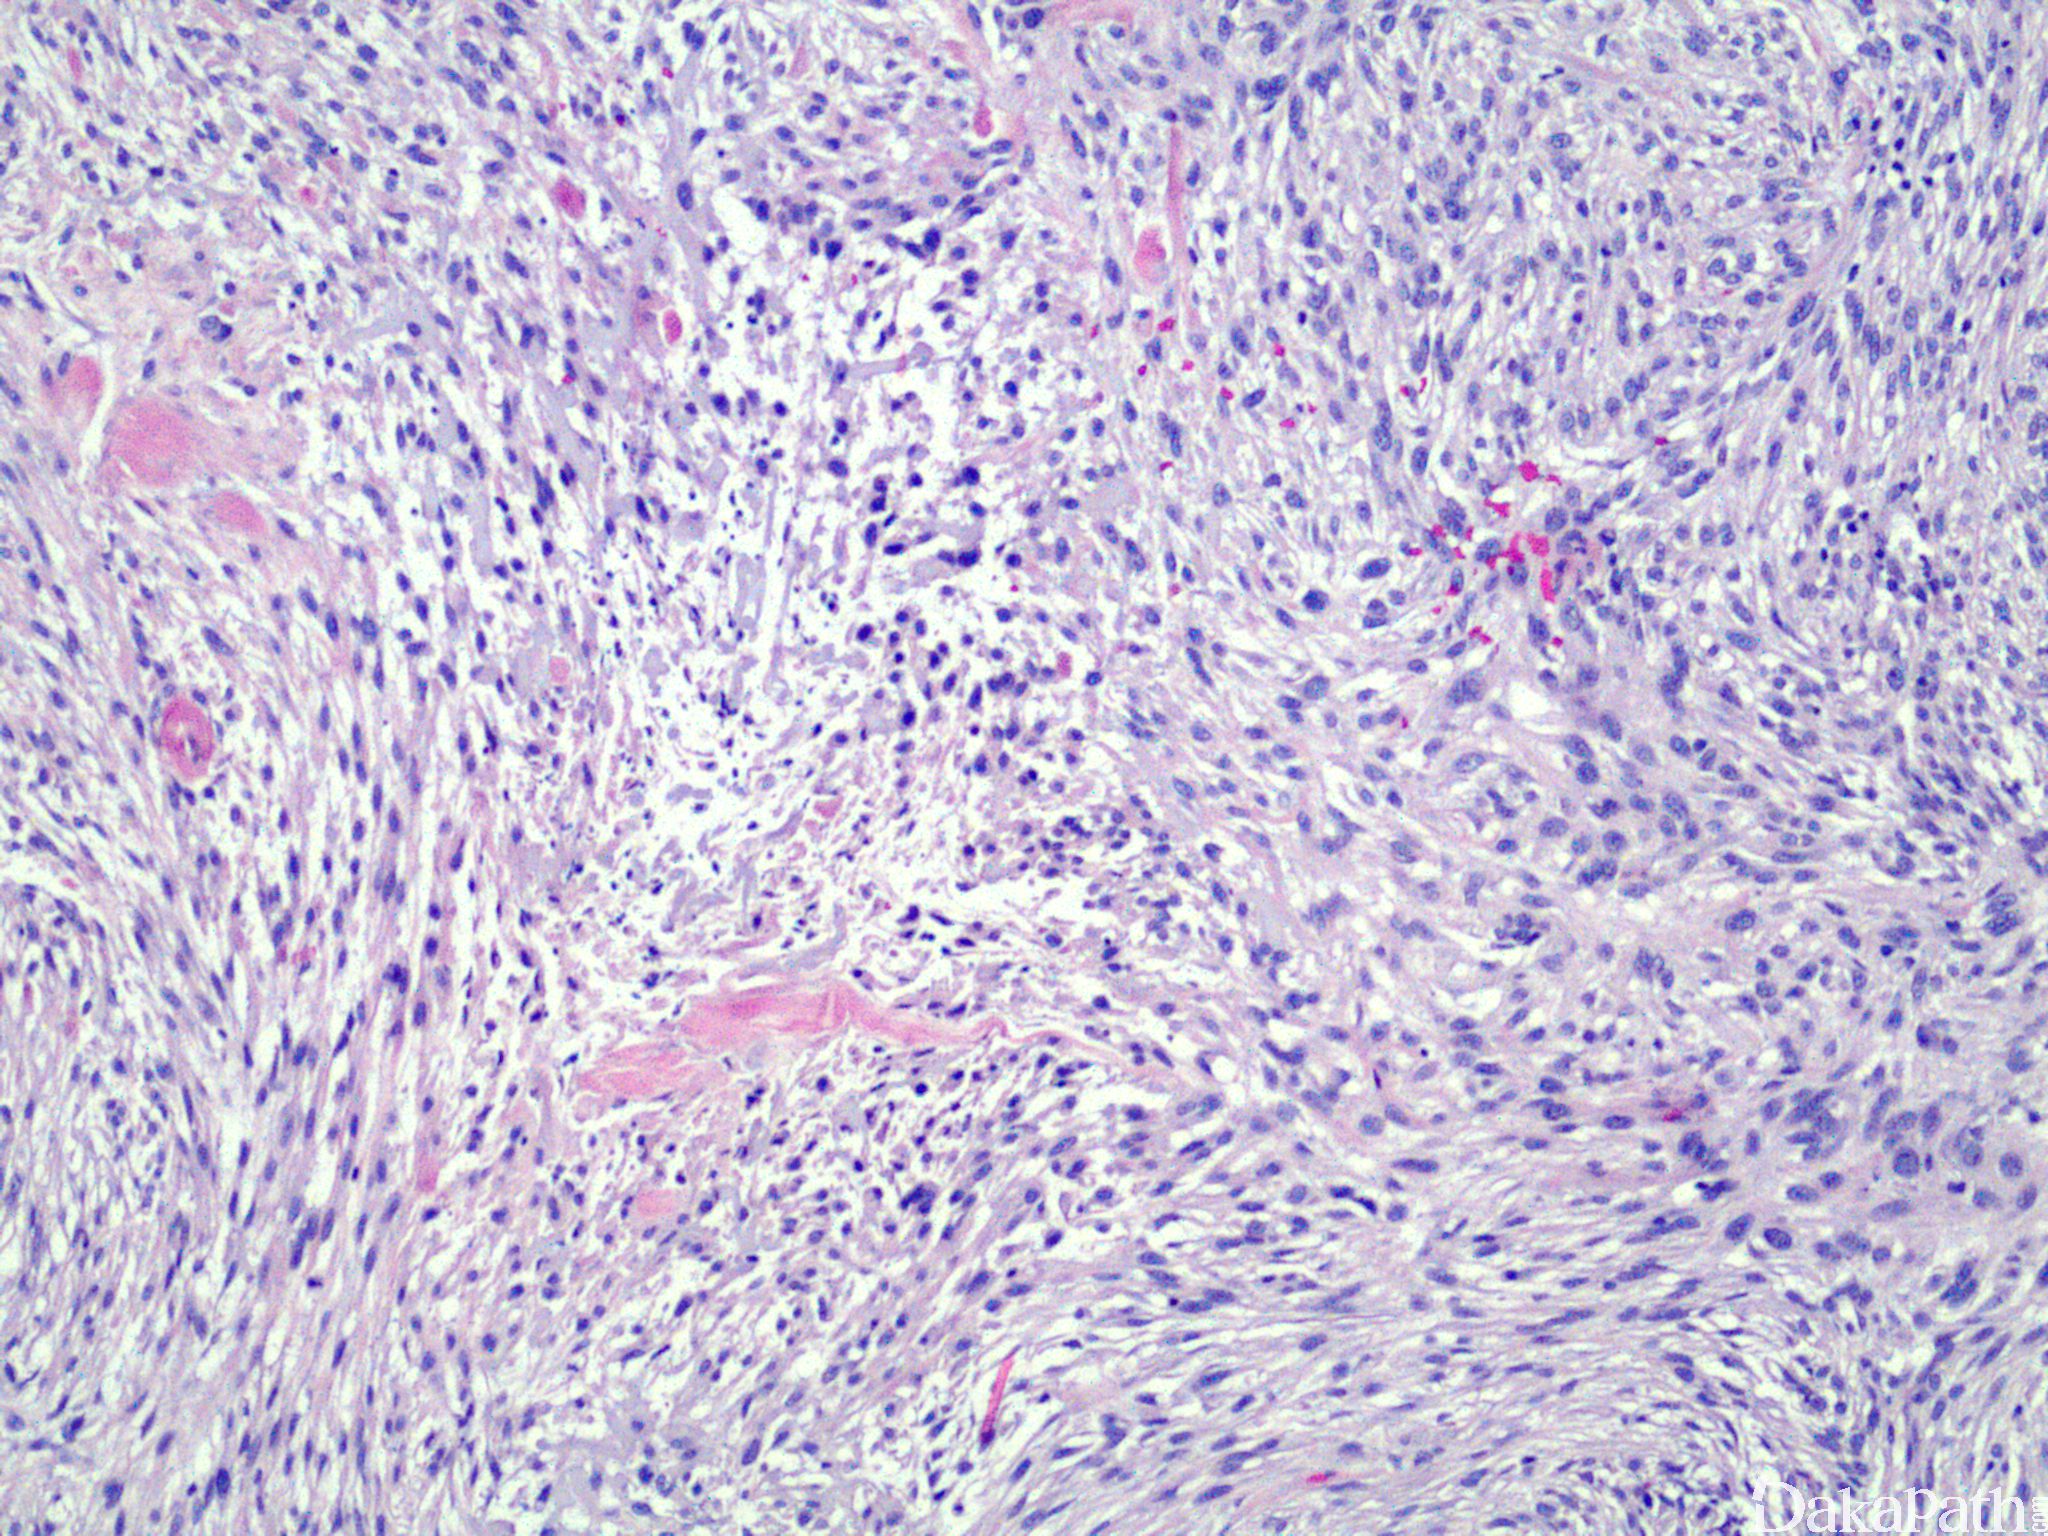

Squamous cell Carcinoma, spindle cell type

在普通鳞状细胞癌形态基础上,细胞形态主要呈梭形,分化较低,缺乏明显角化,需要免疫组织化学染色辅助确诊。